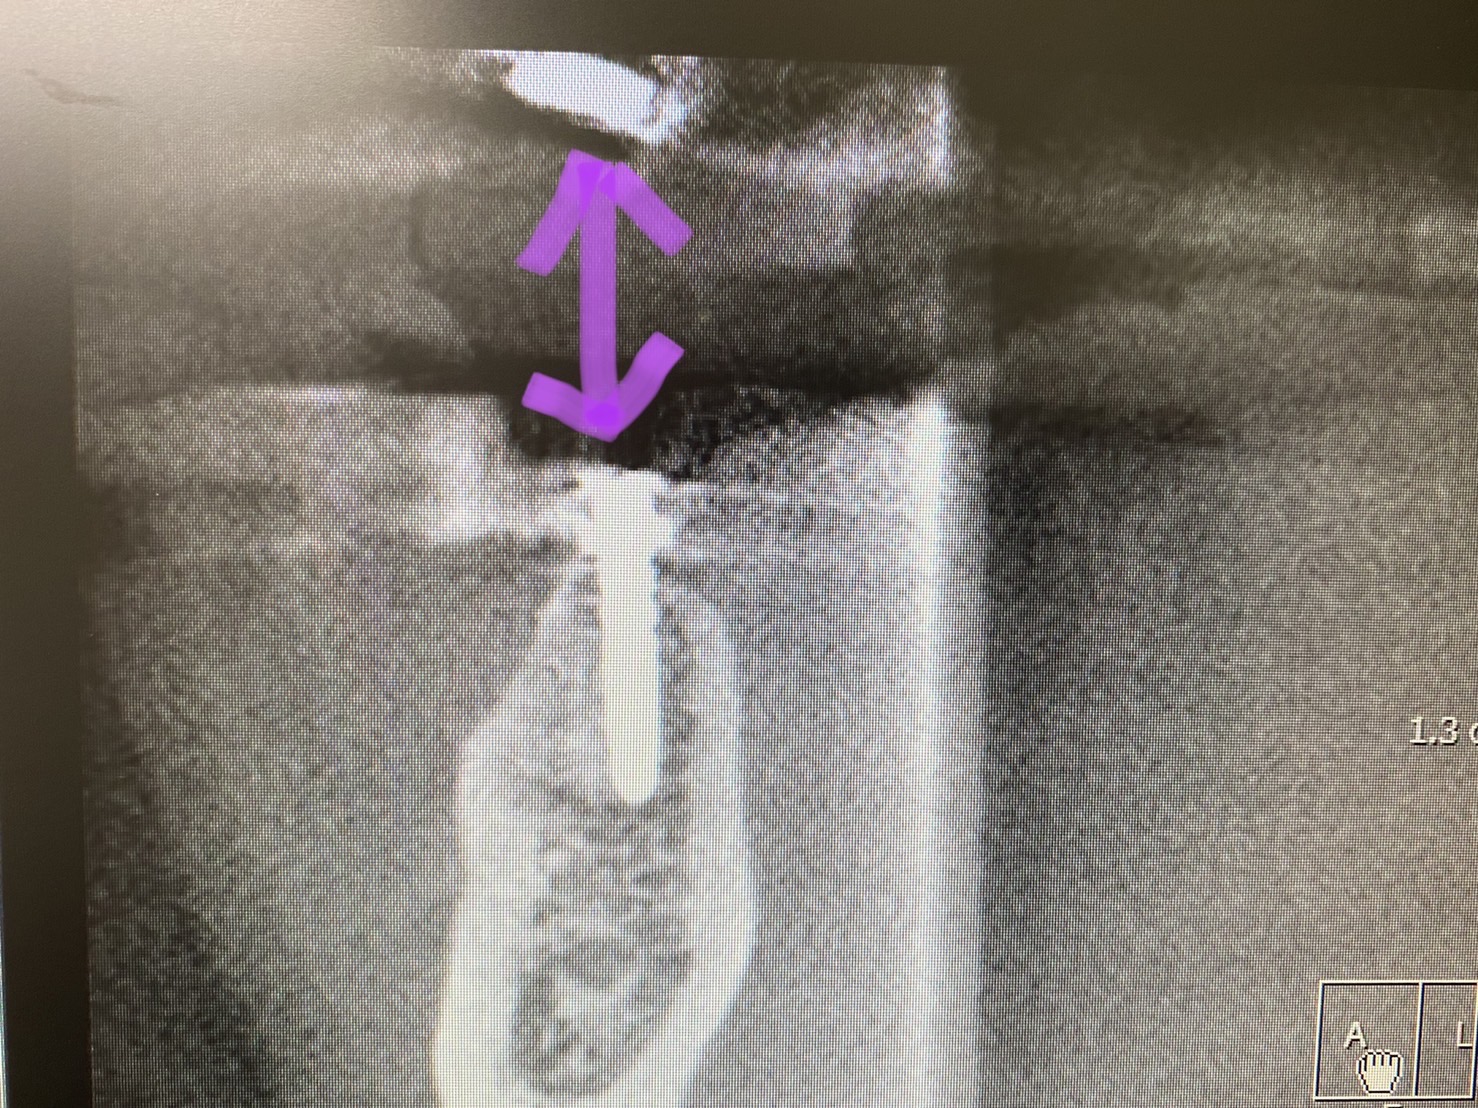

骨質D4

骨質が非常に柔らかいので

オステオデンスフィケーションしながらね!

I SQ値は良かったが、剪断力を示す値がボーダーでしたので、暫しスリーピングで余裕を

フリーだと、骨の感触が非常に分かり易く、途中で試適CT画像で方向を確認。

この時点で必要があれば微細修正可能です